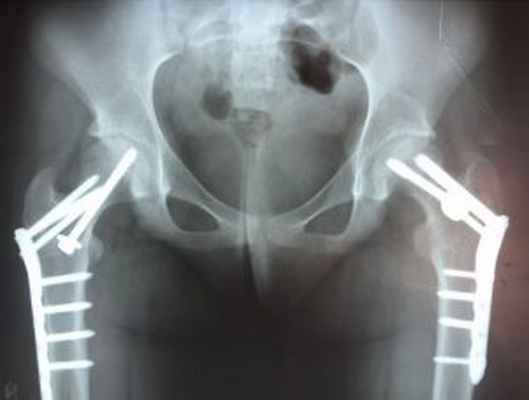

Лечение ЭГБК

Эпифизеолиз головки бедренной кости обычно прогрессирует, он требует хирургического вмешательства при постановке диагноза. Пациенты не должны переносить вес на больную ногу до тех пор, пока ЭГБК (SCFE) не будет исключен или вылечен. Хирургическое лечение состоит в винтовой фиксации через зоны роста.

Лечение юношеского эпифизеолиза

По данным многочисленных исследований, не существует консервативных способов лечения, способных предотвратить соскальзывание головки относительно шейки и нижележащих отделов бедренной кости. Смещение нарастает даже при продолжительной разгрузке и иммобилизации конечности. Поэтому основным методом лечения является хирургическое вмешательство, в ходе которого производится фиксация головки и шейки. Металлоостеосинтез дополняется следующими оперативными методами:

- В случаях раннего выявления болезни и незначительного смещения возможно стабилизация эпифиза головки бедренной кости в правильном положении винтами;

- При позднем выявлении патологии и значительном смещении эпифиза бедренной кости проводятся сложные реконструктивные хирургические вмешательства на бедренной кости.